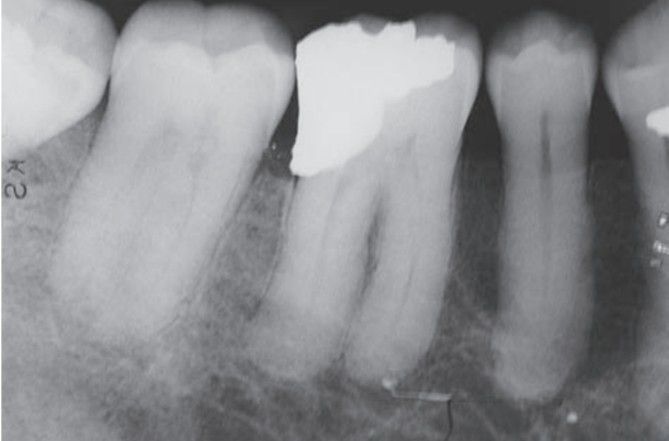

Pagets disease associated with hypercemetosis of mandibular 1st molar.

Hypercementosis in Paget’s disease.